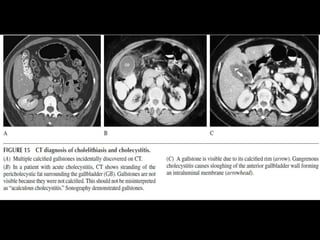

IMAGING DIAGNOSIS OF ACUTE

CHOLECYSTITIS

• Abdominal rx: 15% stones calcified

• Ultrasound : > sensitive

• Symptomatic:

– 80% without

DIAGNOSIS OF ACUTE CHOLECYSTITIS

• CLINICAL PRESENTATION

• SIGNS OF GALLBLADDER INFLAMATION ON

SONOGRAPHY OR CT

– GALLBLADDER WALL THICKENING (>3 TO 5MM)

– PERICHOLECYSTIC FLUID

– SONOGRPHIC MURPHY’S SIGN

IMAGING DIAGNOSIS OFACUTE CHOLECYSTITIS • Abdominal rx: 15% stones calcified • Ultrasound : > sensitive • Symptomatic: – 80% without

DIAGNOSIS OF ACUTECHOLECYSTITIS • CLINICAL PRESENTATION • SIGNS OF GALLBLADDER INFLAMATION ON SONOGRAPHY OR CT – GALLBLADDER WALL THICKENING (>3 TO 5MM) – PERICHOLECYSTIC FLUID – SONOGRPHIC MURPHY’S SIGN